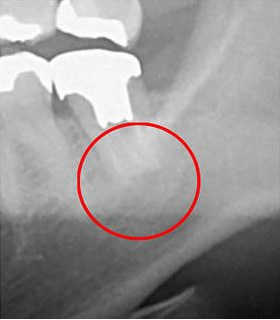

こちらは、同じ部位をCTとレントゲンで撮影したものを比較した画像です。

• 比較

左側はCT画像、右側はレントゲン画像です。赤丸で示した部分に黒い影が確認できますが、これが炎症の起きている部位です。

CTでは確認できますが、レントゲンでは写らず、見落とされることがあります。

レントゲンのみで診断した場合、この炎症に気付かないまま進行し、結果として抜歯に至るケースもあります。

当院ではそのリスクを避けるため、CTによる診断を徹底しています。